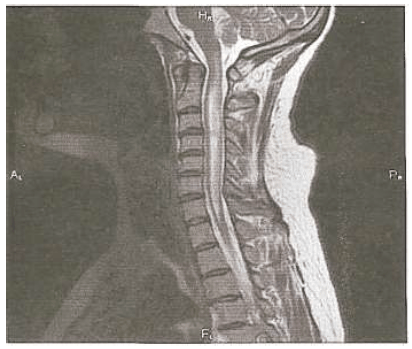

Há dois meses, paciente do sexo masculino, 45 anos, desenvolveu perda de visão quase completa no olho esquerdo, que não se resolveu apesar do uso de pulsoterapia com solumedrol, acompanhado por um ciclo de esteroides orais que foram progressivamente retirados. Duas semanas atrás, ele desenvolveu perda visual no olho direito, que persistiu. Relata parestesias com queimação em ambos os pés e alguma urgência urinária, ambas presentes há 1 ano. A RM da medula cervical é apresentada abaixo. Seu líquido cefalorraquidiano demonstra 50 leucócitos/mm3, com 45% de neutrófilos, 55% de linfócitos, proteína de 75 mg/dL e bandas oligoclonais negativas. O VDRL no LCR é negativo, HTLV I e II são negativos e o nível de vitamina B12 é normal. A ANA é moderadamente elevada em um título de 1:128.